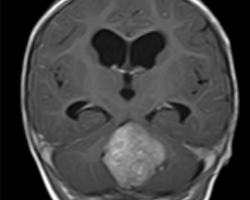

Un enfant de 6 ans est emmené par ses parents aux urgences pédiatriques pour des vomissements incoercibles. L’enfant se plaint depuis plusieurs semaines de céphalées, mal soulagées par la prise de paracétamol.